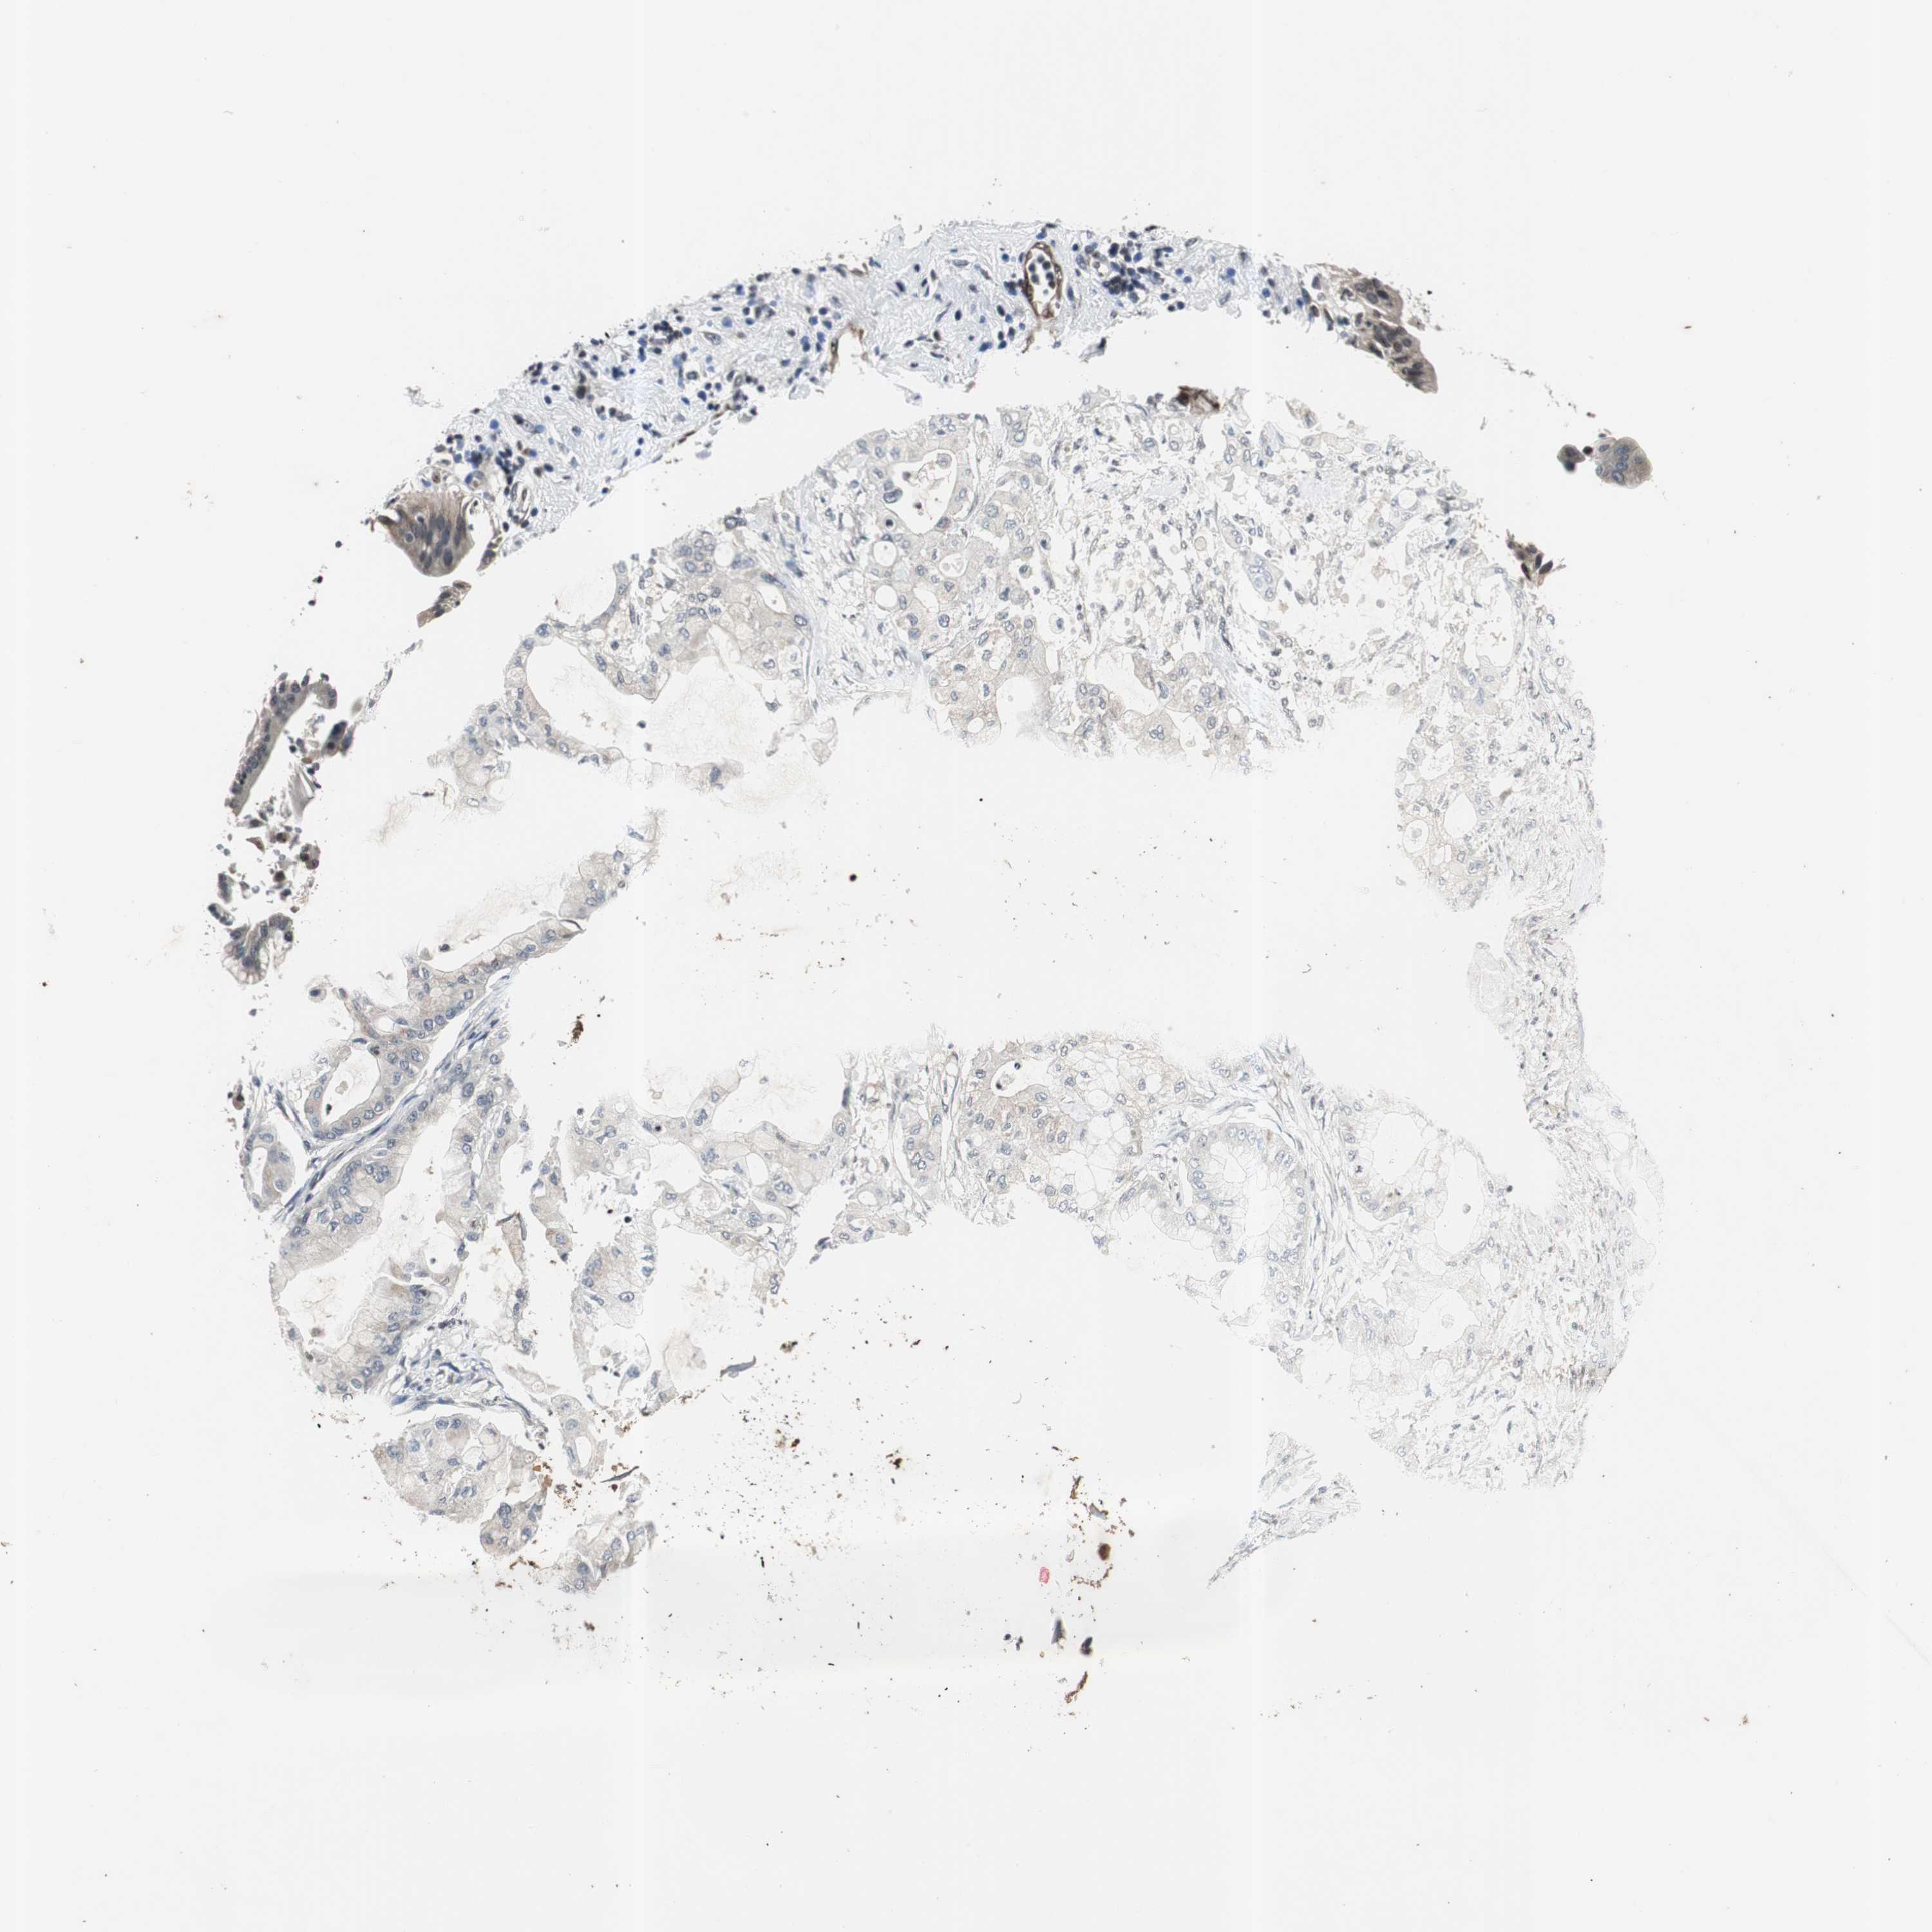

PANCREATIC CANCER - Protein expressioni

A mouse-over function shows sample information and annotation data. Click on an image to view it in a full screen mode. Samples can be filtered based on level of antibody staining by selecting one or several of the following categories: high, medium, low and not detected. The assay and annotation is described here.

Note that samples used for immunohistochemistry by the Human Protein Atlas do not correspond to samples in the TCGA dataset.

Antibody stainingi

Antibody staining in the annotated cell types in the current human tissue is reported as not detected, low, medium, or high, based on conventional immunohistochemistry profiling in selected tissues. This score is based on the combination of the staining intensity and fraction of stained cells.

Each image is clickable and will lead to virtual microscopy that enables deeper exploration of all samples and also displays staining intensity scores, fraction scores and subcellular localization as well as patient and tissue information for each sample.

Antibody CAB005389

Staining

High

Medium

Low

Not detected

Intensity

Strong

Moderate

Weak

Negative

Quantity

>75%

75%-25%

<25%

None

Location

Nuclear

Cytoplasmic/membranous

Cytoplasmic/membranous,nuclear

Adenocarcinoma, NOS

Adenocarcinoma, metastatic, NOS